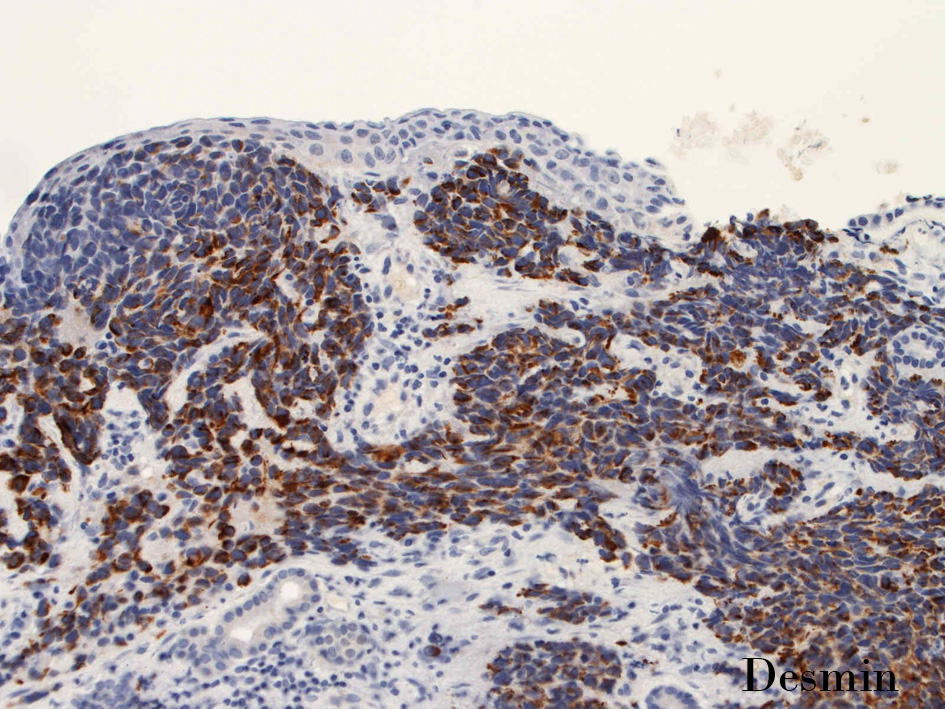

免疫染色

Desmin.jpg

Desmin_02.jpg

DesminDesminmyogenin

small round cell tumorの中でrhabdomyosarcomaは腫瘍細胞に種々の抗原が陽性となるため診断を誤ることがあり注意が必要である*1

*1 Bahrami A, et al., Aberrant expression of epithelial and neuroendocrine markers in alveolar rhabdomyosarcoma: a potentially serious diagnostic pitfall. Mod Pathol. 2008 Jul;21(7):795-806. Epub 2008 May 16. PMID:1848799199